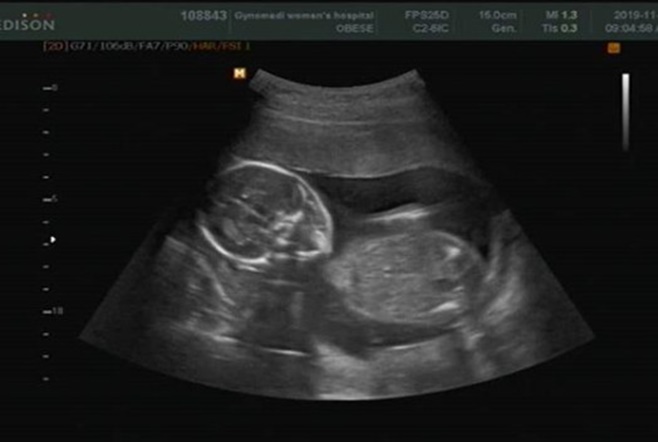

[ƼºêÀ̵¥Àϸ® ¿ÀÁö¿ø ±âÀÚ] ¹êµå Àͽº(EX) Ãâ½Å ÀÌ»ó¹Ì°¡ ÀӽŠÈÄ ±ÙȲÀ» ¹àÇû´Ù. ÀÌ»ó¹Ì´Â 5ÀÏ SNS¸¦ ÅëÇØ "¸¹Àº ÃàÇÏ °¨»çµå¸³´Ï´Ù. ±Ù·¡ ´Ùµé Á¦°Ô »ìÀÌ ¿Ö ÀÌ·¸°Ô ºüÁ³³Ä°í, ¾îµð ¾ÆÇÁ³Ä°í Çϼ̴µ¥ ÀӽŠÃʱ⿡ ÀÔµ¡ÀÌ ³Ê¹« ½ÉÇØ¼ »ìµµ 5kgÀ̳ª ºüÁö°í žƵµ ¾ÈÁ¤À» ãÁö ¸øÇؼ À§ÇèÇÑ ¼ø°£µéÀÌ ¸¹¾Ò¾î¿ä"¶ó¸ç ±ÙȲÀ» ÀüÇß´Ù. ÀÌ»ó¹Ì´Â "°È´Â °Íµµ Á¶½ÉÁ¶½É ¾îÂ ¸¾ Á¹À̸ç ÇÏ·çÇϷ縦 º¸³Â´øÁö. ÀÌ·¨´ø À̵çÀ̰¡ ÀÌÁ¦´Â °Ç°ÇÏ°Ô ¾¦¾¦ ÀÚ¶ó¼ 21ÁÖ¸¦ ÇâÇØ°¡°í ÀÖ´Ù. ¾ÈÁ¤ÀûÀ¸·Î Àß ÀÚ¶ö ¶§±îÁö ¼ÖÁ÷ÇÏ°Ô ¿ÀÇÂÇØ¼ ¸»¾¸µå¸®Áö ¸øÇß´ø Á¡ Á˼ÛÇÕ´Ï´Ù"°í ¹àÇû´Ù.

Ã⿬ ÁßÀÌ´ø ÇÁ·Î±×·¥ÀÇ Á¦ÀÛÁø¿¡ ´ëÇÑ °í¸¶¿òÀÇ Àλ絵 »©³õÁö ¾Ê¾Ò´Ù. ÀÌ»ó¹Ì´Â "±×·± Àú¸¦ ½¯ ¼ö ÀÖµµ·Ï ¹è·ÁÇØÁÖ°í ÀÀ¿øÇØÁֽŠtbs '´õ·ë' '¶óµð¿À¸¦ ÄѶó Á¤¿¬ÁÖÀÔ´Ï´Ù', KBS '±è¿øÁØÀÇ ¶óµð¿À½ºÅ¸' Á¦ÀÛÁø ºÐµé, ¾ð´Ï¿Àºüµé Á¤¸» °¨»çµå·Á¿ä"¶ó°í ¸»Çß´Ù. À̾î "±ÞÇÏ°Ô ÇÏÂ÷ÇÏ¸é¼ Àúµµ ³Ê¹« ´«¹°ÀÌ ³µÁö¸¸ ±×¶© ÁøÂ¥ ¿ì¸® À̵çÀ̸¦ ¾î¶»°Ôµç ¹è¿¡ ²À ºÙ¾îÀÖ°Ô ÇØ¾ß°Ú´Ù´Â »ý°¢ »ÓÀ̾ú¾î¿ä. ÀÀ¿øÇØÁֽŠ¿©·¯ºÐ²²µµ °¨»çµå¸®°í ³»³â 4¿ù±îÁö ¸öµµ °Ç°, ¸¶À½µµ °Ç°ÇÏ°Ô Å±³ Àß Çϰí ÀÖÀ»°Ô¿ä"¶ó°í µ¡ºÙ¿´´Ù. ³¡À¸·Î "¾ö¸¶°¡ ¼¿ï ´ë±¸ ¿Ô´Ù°¬´ÙÇÏ¸é¼ ³ìÈÇϴµ¥µµ Àß ¹öÅßÁÖ°í ÀÖ´Â ¿ì¸® À̵çÀ̵µ °í¸¶¿ö"¶ó¸ç ¾ÆÀÌ¿¡ ´ëÇÑ ¾ÖÁ¤À» µå·¯³Â´Ù. ÀÌ¿Í ÇÔ²² ÀÌ»ó¹Ì´Â ÅÂ¾Æ ÃÊÀ½ÆÄ »çÁø°ú ¿µ»óÀ» °ø°³Çß´Ù. ÀÌ»ó¹Ì´Â Áö³´Þ 23ÀÏ °áÈ¥½ÄÀ» ÁøÇàÇϰí, º£Æ®³²À¸·Î ½ÅÈ¥¿©ÇàÀ» ´Ù³à¿Ô´Ù. [ƼºêÀ̵¥Àϸ® ¿ÀÁö¿ø ±âÀÚ news@tvdaily.co.kr / »çÁø=´õºíºêÀÌ¿£ÅÍÅ×ÀÎ¸ÕÆ®, ÀÌ»ó¹Ì ÀνºÅ¸±×·¥] |